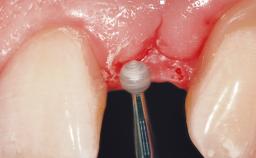

This 43-year-old male patient, a non-smoker, came to our practice because of a fracture of tooth 12 caused by a bicycle accident. Due to the combined para- and infrabony crown and root fracture, tooth extraction, and subsequent implant placement were suggested to the patient as the therapy of choice. The patient had high esthetic expectations with regard to the treatment outcome and asked for an immediate fixed provisional restoration. His individual esthetic risk profile summed up to a medium esthetic risk.